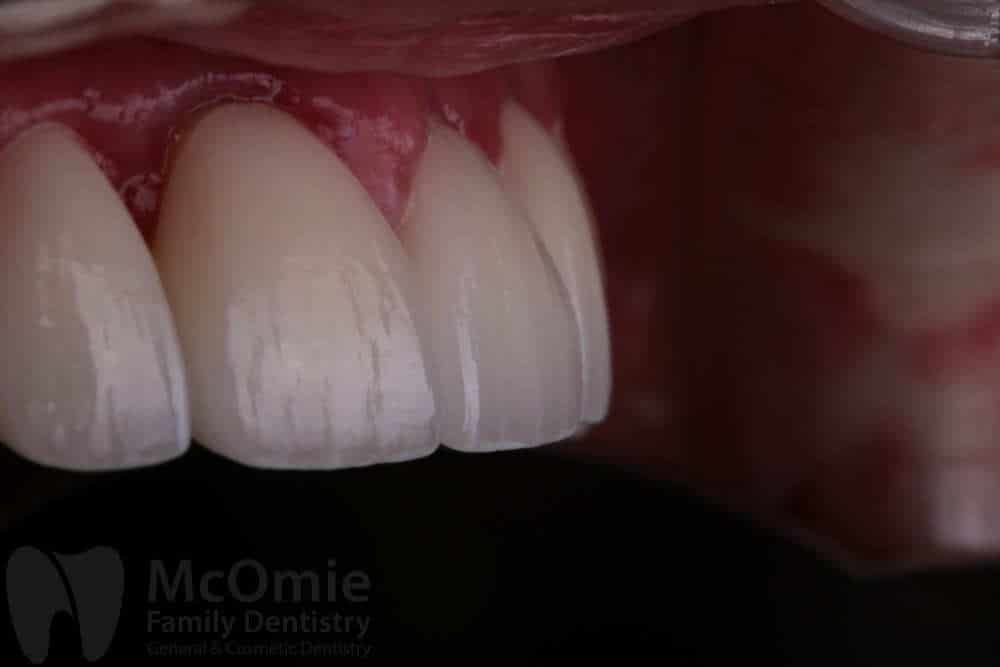

This case involved restoring two front teeth after a fall caused facial trauma and significant damage to the smile. The injury resulted in fractured front teeth and irregular gum contours. Treatment included placing two custom crowns along with gum contouring to refine the shape of the tissue and improve symmetry. The restorations were carefully crafted by our master ceramists to match natural tooth structure, color, and detail. The result is a seamless, natural-looking smile with both aesthetics and function fully restored.